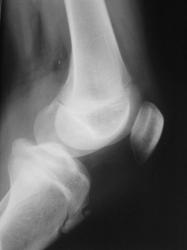

Кислое дело, этот самый Осгут-Шлаттер, особенно без второго сустава. Как Вы напишите, так и будет. Особенно, если напишите "за". Опровергнуть будет почти невозможно. Но второй сустав в боковой проекции надо сделать обязательно.

Считаю, что - норма (контуры ровные четкие, структура однородная, щели равномерной ширины)

Андрей Юрьевич! По поводу второго сустава соглашусь. Но иногда бывает и односторонняя остеохондропатия.

Большое спасибо коллеги за высказанные мнения. А вариантом нормы "сие" может быть?